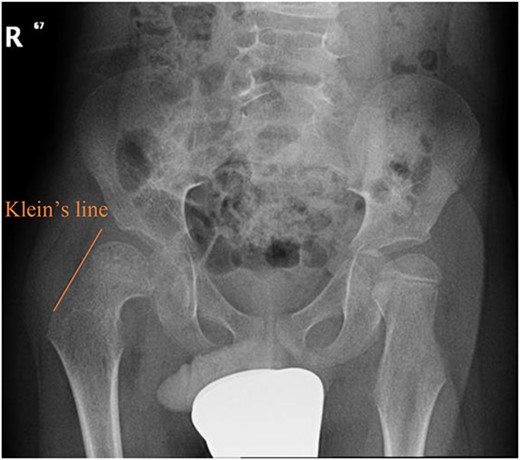

A 5-year-old independent ambulatory Middle Eastern boy with CP who was born preterm and developed grade III intraventricular haemorrhage and periventricular leucomalacia and was on AEDs, including valproic acid (VPA) and levetiracetam (LEV), for >3 years and was controlled over the last year (no history of seizure attack) presented to the emergency room (ER) with right hip pain and inability to bear weight for 4 weeks; the patient had no history of fever or trauma. Physical examination shows a thin, the weight is 12 kg, the height is 101 cm, vital signs within the normal range, tenderness over the right hip, and external rotation of the right hip, with restricted hip mobility. A radiological study was performed ~3 months before the patient presented to the ER for follow-up examination of a left hip coxa valgus deformity with no apparent abnormalities in the right hip (Fig. 1). Initial imaging studies conducted in the ER showed an anterior–posterior view of the pelvic radiograph, revealing Klein’s line [13] not intersecting the capital femoral epiphysis (Fig. 2), and frog-leg lateral view radiograph of the right hip (Fig. 3) confirmed SCFE and Southwick’s slip angle [13] of ~50° (moderate). Laboratory findings were clear for endocrine and renal diseases or infection, except for low vitamin D (total 25-OH Vitamin D: 43.4 nmol/L), suggesting vitamin D insufficiency. The diagnosis was confirmed with clinical and radiological studies as right-sided unstable SCFE requiring surgery. Surgical intervention was performed with percutaneous in situ fixation using a single fully threaded 4.5-mm cannulated screw (Fig. 4). Postsurgical rehabilitation included non-weight-bearing right lower extremities for 6 weeks. Regular follow-up with serial radiology studies showed stable fixation with no migration of screw or further slippage at 6 weeks (Fig. 5) and 3 (Fig. 6), 15 (Fig. 7), and 36 months (Fig. 8). During follow-up, a painless range of motion in the right hip was observed, with full weight-bearing and resumption of his usual activities with no complaints.

Pelvic anterior–posterior radiograph showing SCFE in the right hip, with Klein’s line not intersecting the capital femoral epiphysis